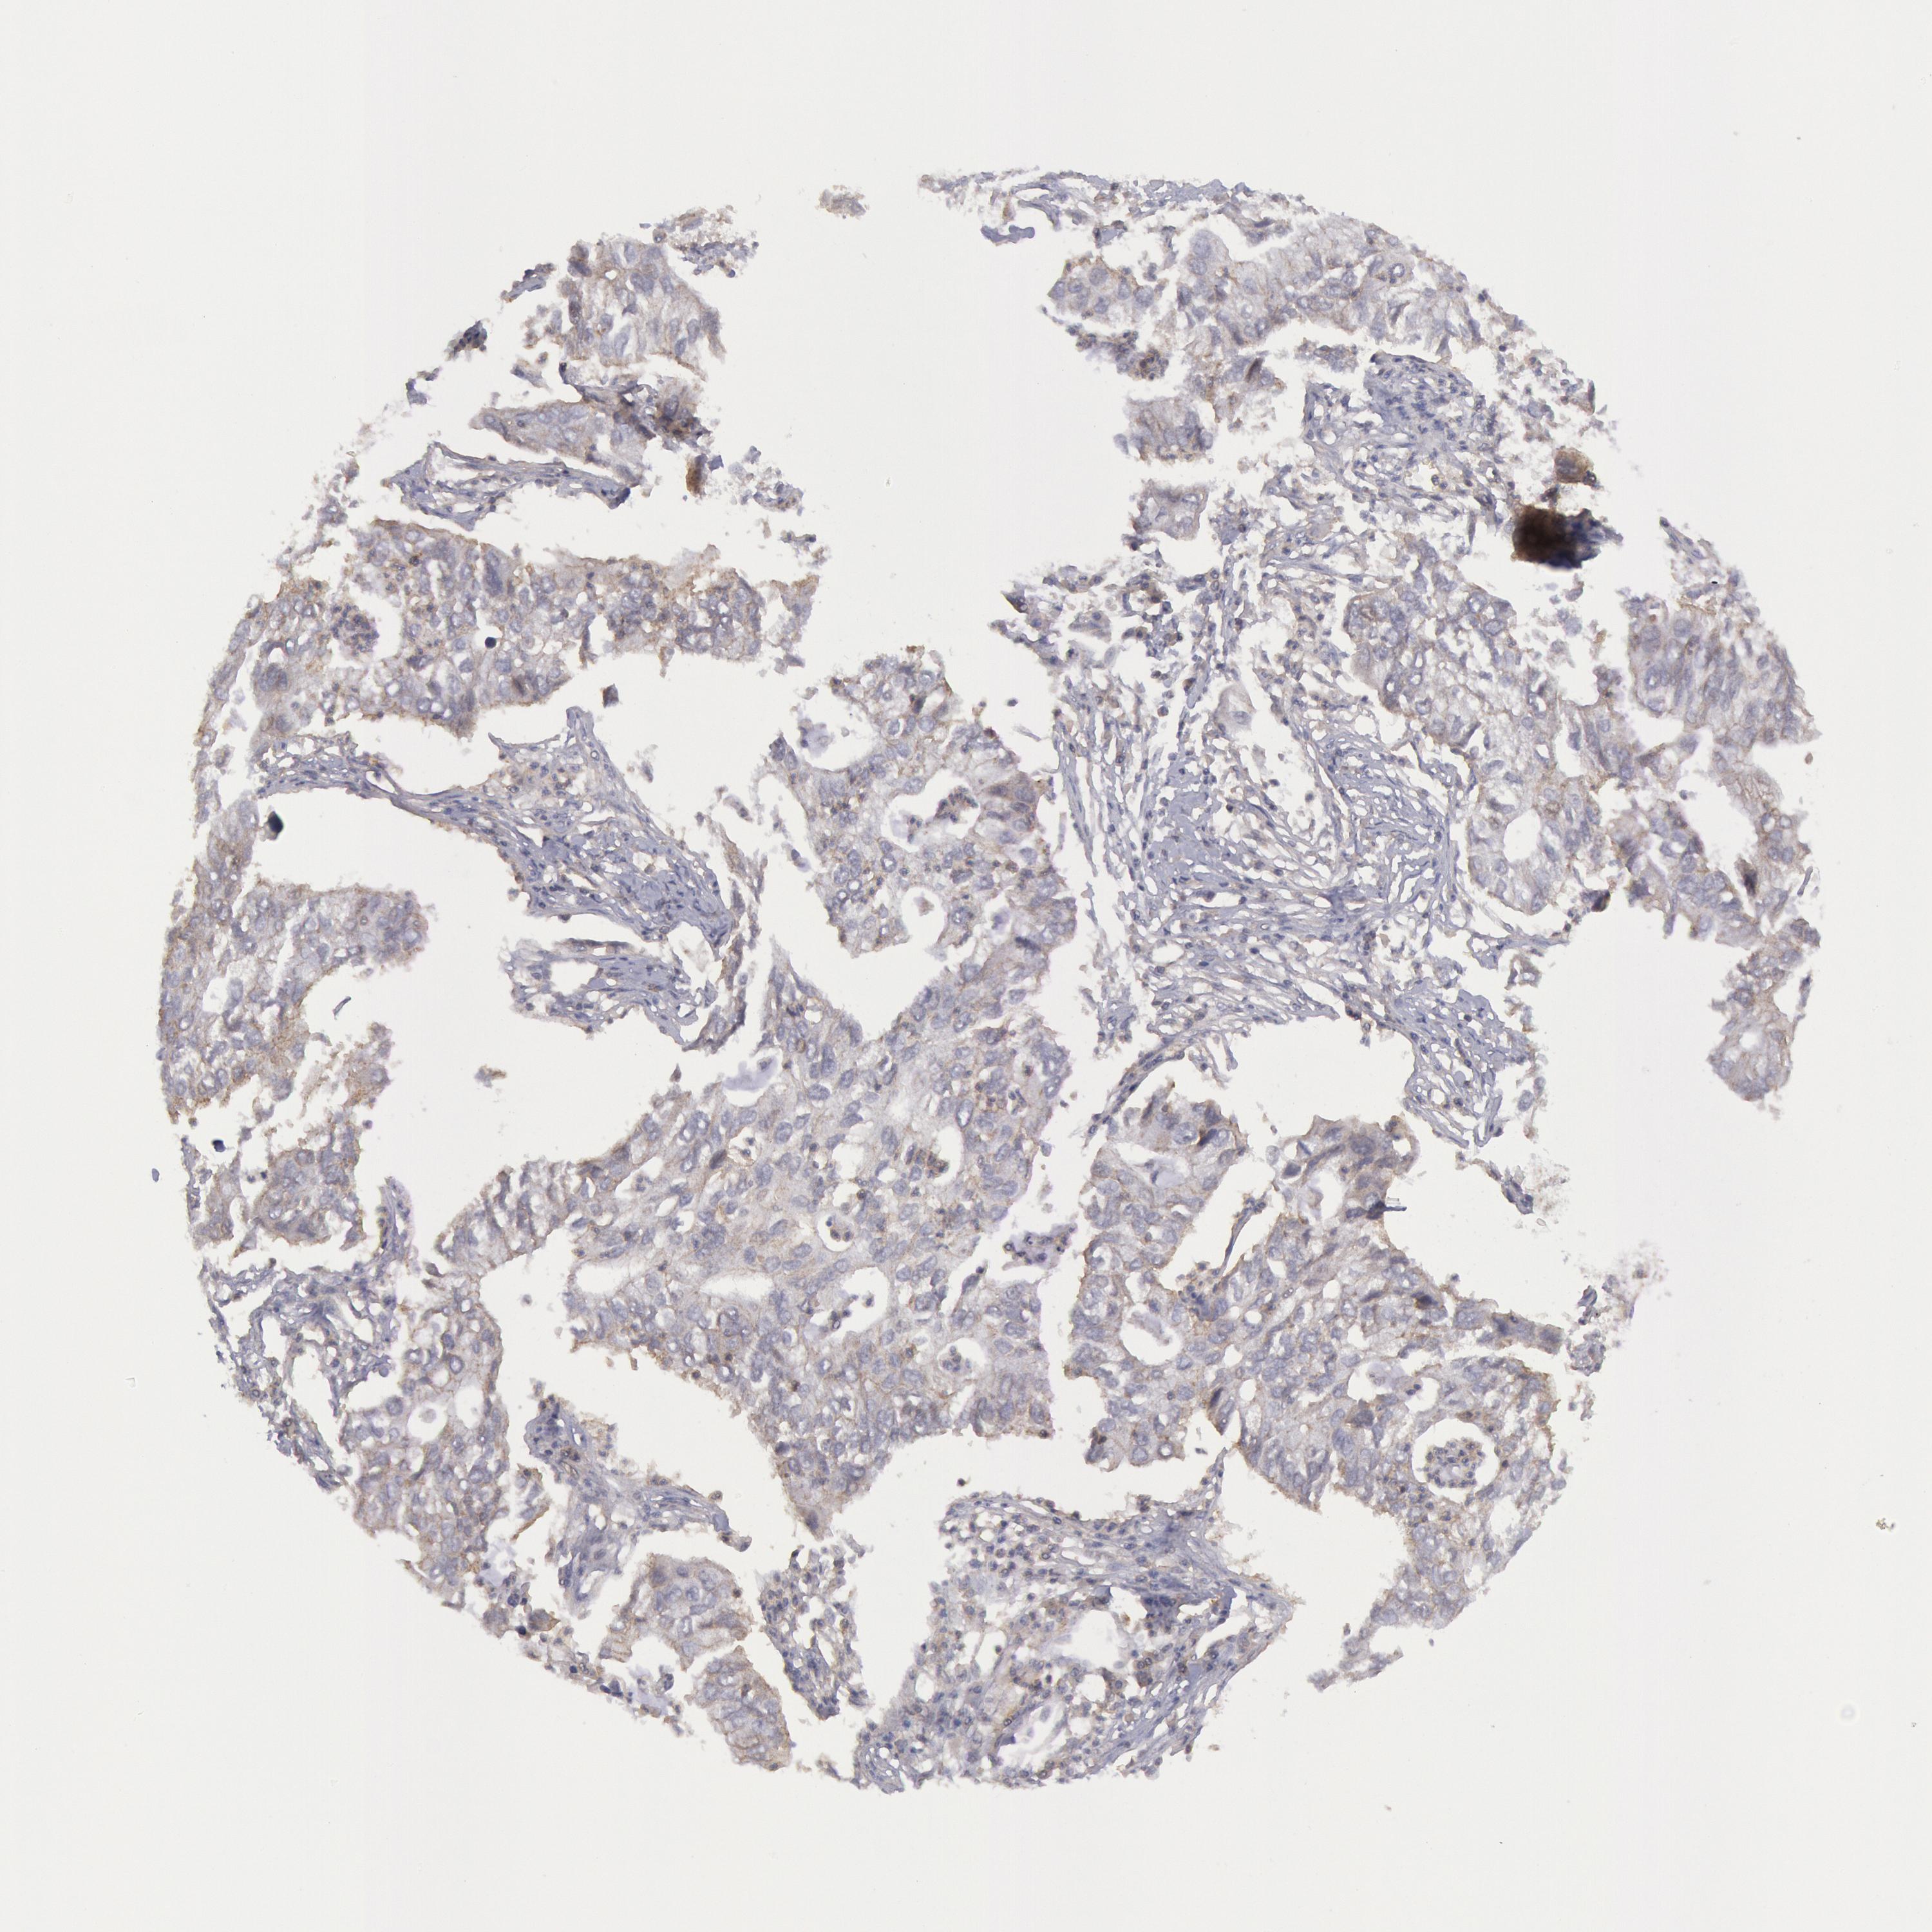

STX4